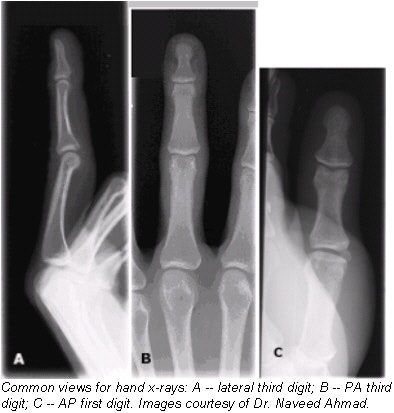

![]() |